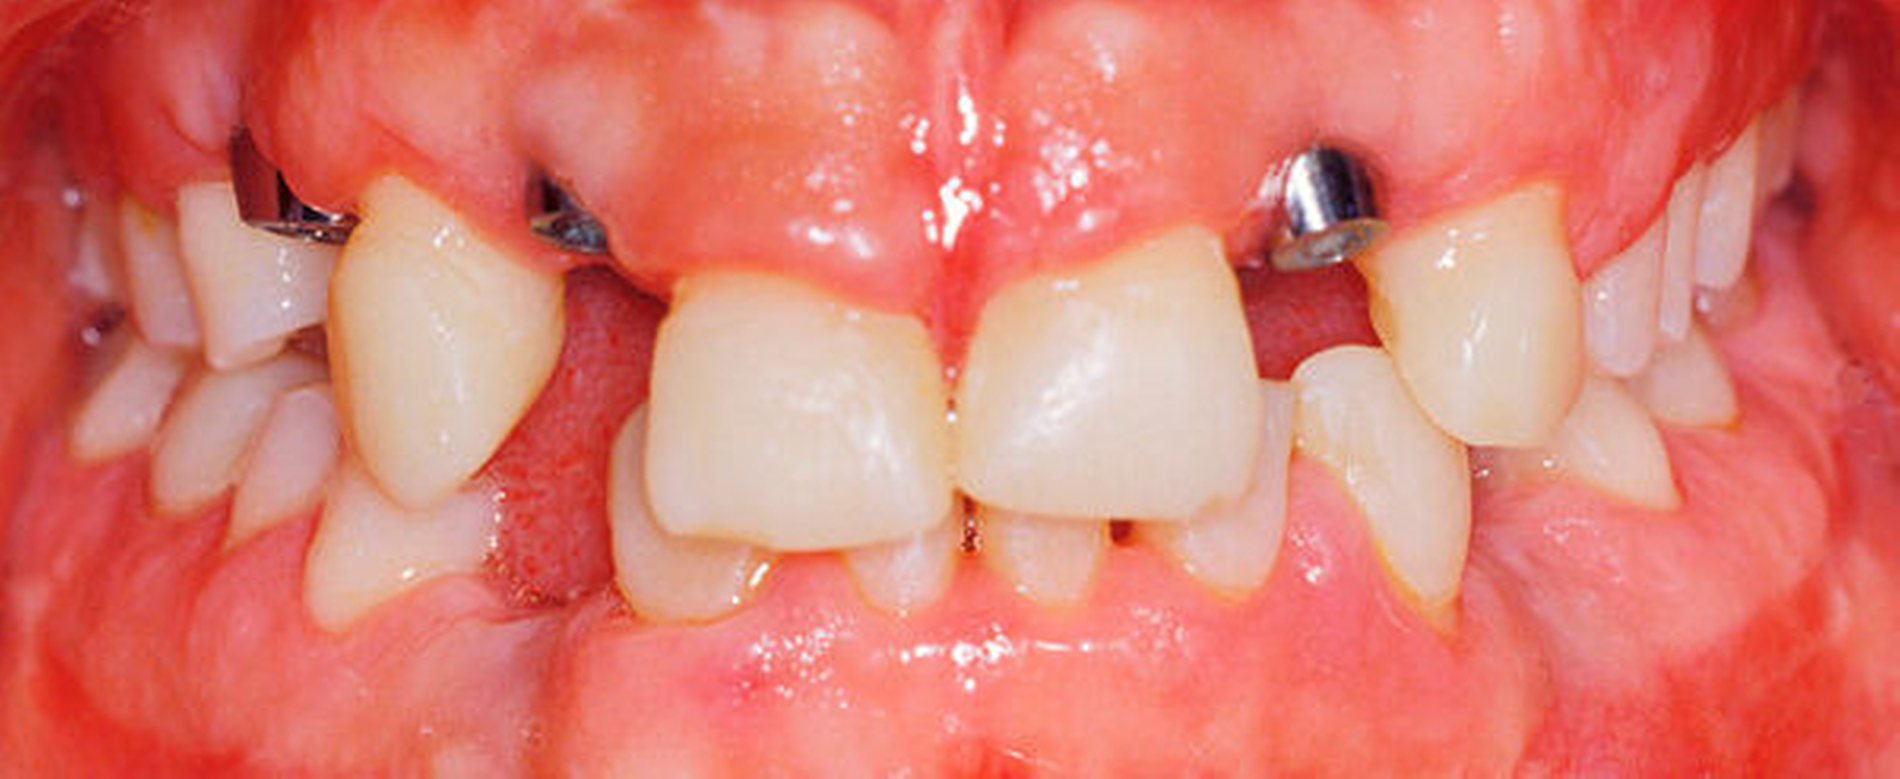

In mehreren Schritten wurden circa vier bis zwölf Monate später in Lokalanästhesie Implantate in den Regionen 12 und 22 (Straumann Narrow Neck) sowie 14, 33 und 44 (Straumann Regular Neck) gesetzt (Abbildung 8a). Zur Verlängerung der kurzen klinischen Kronen 11 und 21 wurde in diesem Bereich die Gingiva im Sinne einer Konturierung elektrotomiert (Abbildung 8b).